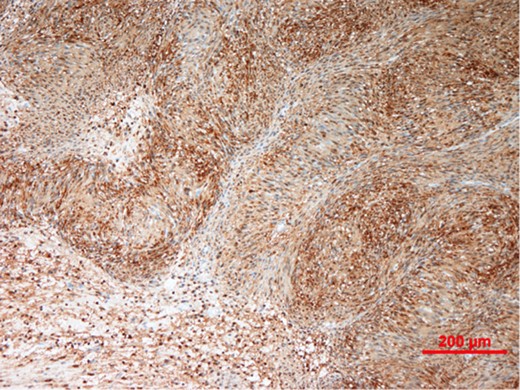

Our patient underwent an excisional biopsy without a preoperative needle biopsy. A 1.2 × 1.2 × 0.8 cm smooth well-encapsulated nodule was removed in entirety from the breast parenchyma. On bisection, the cut section displayed a pale pink smooth homogeneous appearance. Microscopic evaluation showed an encapsulated spindle cell tumour with prominent nuclear palisading and features typical of a schwannoma (Fig. 3). There was also strong and diffuse positive staining of S-100, favouring the diagnosis of schwannoma (Fig. 4). There was no evidence of malignancy in the specimen.

Spindle cell tumour with palisaded arrangement of nuclei, typical of schwannoma. Cellular (Antoni A) areas alternate with looser myxoid (Antoni B) areas.